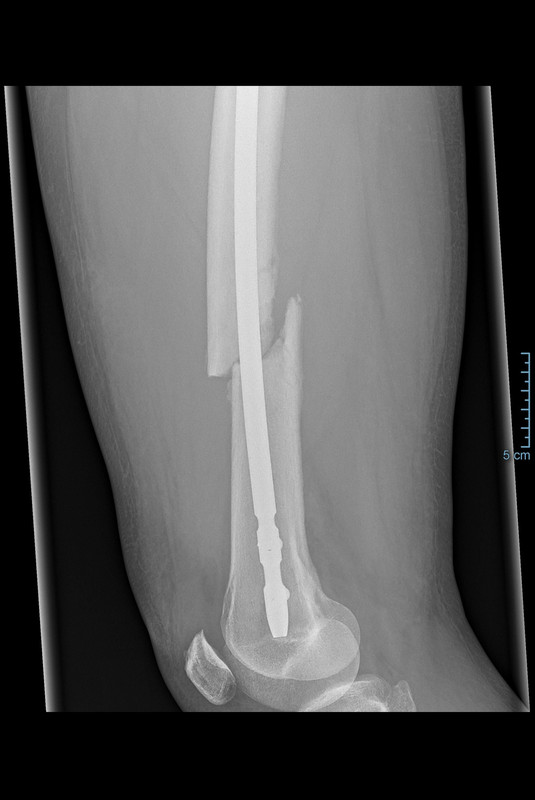

Der Oberschenkelknochen war gebrochen.

In einer "Not"-OP (KH Zams/Tirol) wurde ein Nagel mit 3 Schrauben eingebracht, um den Bruch zu stabilisieren.

Leider sitzen die Knochenenden nicht regelrecht aufeinander.

Der empfahl, dass die Schrauben und der Nagel wieder raus sollen, der Knochen von innen weiter aufgefräst wird, um einen dicker Nagel (14mm) einzubringen.

Derzeit ist ein 11mm Nagel drin. Gleichzeitig soll die "wenig" gebildende Knochenmasse wieder rausgenommen werden (zusätzlicher, seitlicher Schnitt).

Die Bruch teilt sich auf: 2/3tel oben, 1/3tel unten.

Die Bruchstelle soll wohl auch deshalb schlecht heilen, weil

a.) der Spalt zu groß ist und

b.) der Knochen an dieser Stelle schlecht durchblutet ist und somit wenig Knochenheilung (Kallus) stattfinden kann.

Alternativ werden die beiden knienahen Verriegelungsschrauben entfernt und von vorne eine Schraube in das dort befindliche Langloch verschraubt, um mehr Bewegung/Kompression/Mobilisierung zu erzeugen.